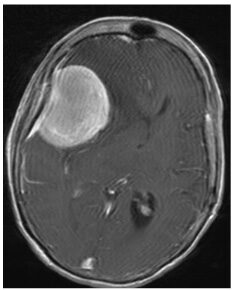

MRI of large right frontotemporal

meningioma causing severe brain compression